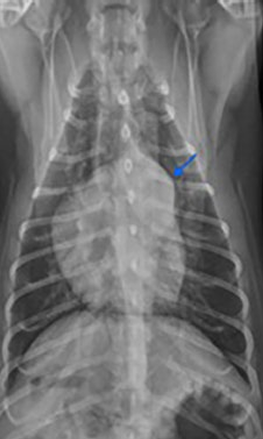

VD

arrow pointed the THYMUS